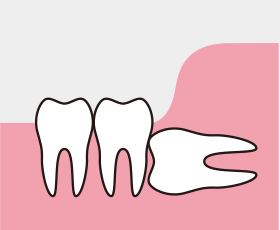

3.傾斜タイプ

歯周炎のリスクが高い

抜歯を検討